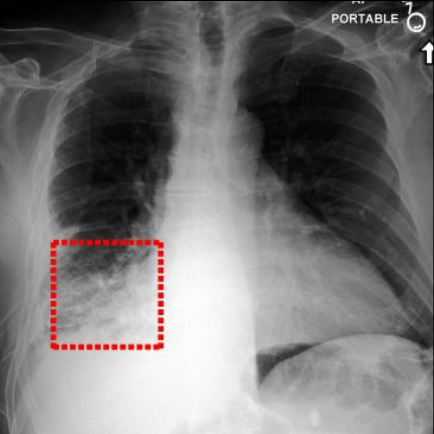

Additional qualitative results, including further visualization examples of text-to-image alignment and iterative refinement, can be found in Figure 7. These examples further illustrate the progressive improvement in localizing lesion regions and associating them with key phrases, reinforcing the effectiveness of PLAN’s iterative refinement strategy.

ID Original First Iteration Second Iteration Third iteration

eg.1 Refer to caption Refer to caption Refer to caption Refer to caption

Increasing bibasilar opacities which could be seen with lower airway inflammation or infection, although developing bronchopneumonia is not entirely excluded. Mild anterior wedge compression deformity of a vertebral body at the thoracolumbar junction, likely L1; although probably chronic, potentially increased somewhat. increasing bibasilar could with lower airway inflammation infection developing bronchopneumonia not entirely excluded mild anterior wedge compression deformity of vertebral body thoracolumbar junction likely probably chronic increased somewhat. increasing bibasilar could lower airway inflammation infection bronchopneumonia not excluded compression deformity vertebral body thoracolumbar junction chronic somewhat. increasing bibasilar lower airway inflammation bronchopneumonia not excluded deformity vertebral thoracolumbar junction chronic.

eg.2 Refer to caption Refer to caption Refer to caption Refer to caption

There is a right-sided pleural effusion that blunts the right-sided lateral pleural sinus but extends into the posterior pleural spaces, occupying the area posterior to the stent prosthesis along the right posterior chest wall. The amount of pleural effusion has increased in comparison with the preceding AP single view chest examination of. The left-sided hemithorax demonstrates unchanged findings with regard to pulmonary vasculature and absence of any new acute infiltrates. a right-sided pleural effusion blunts right-sided lateral pleural extends posterior pleural spaces posterior the stent prosthesis right posterior chest wall amount pleural effusion increased in comparison single view chest examination left-sided hemithorax demonstrates unchanged regard pulmonary vasculature absence any acute infiltrates. right-sided pleural effusion blunts lateral pleural extends posterior spaces posterior prosthesis wall pleural effusion increased single view chest left-sided hemithorax demonstrates unchanged pulmonary vasculature absence acute infiltrates. right-sided pleural effusion blunts pleural extends posterior spaces prosthesis wall pleural effusion increased view chest left-sided hemithorax unchanged pulmonary vasculature absence infiltrates.

eg.3 Refer to caption Refer to caption Refer to caption Refer to caption

Two right basilar chest tubes remain in place. There is a stable small right apical pneumothorax. Contiguous patchy airspace disease at the right base is also seen and stable. There is a small residual right pleural effusion vs. pleural thickening, unchanged. Left lung is clear. No evidence of pulmonary edema. Heart remains enlarged. Mediastinal contours are unchanged. two right basilar chest tubes remain there stable small right apical pneumothorax contiguous patchy airspace disease right also seen stable a small residual right pleural effusion Pleural thickening unchanged left lung clear no evidence pulmonary edema heart remains enlarged mediastinal contours are unchanged. two chest tubes remain small right apical pneumothorax patchy airspace disease right stable residual right pleural effusion pleural thickening unchanged left lung clear no evidence pulmonary edema heart enlarged mediastinal contours unchanged. two tubes right apical pneumothorax patchy disease pleural effusion pleural thickening unchanged left lung clear no edema heart enlarged mediastinal contours unchanged.

Figure 7: Iteration Effect Analysis. Visualization of text-to-image alignment and its refinement over multiple iterations on the MS-CXR dataset. Each example demonstrates the progressive improvement in localizing lesion regions and associating them with key phrases as iterations increase. The alignment becomes more accurate and precise, reflecting the effectiveness of PLAN’s iterative refinement strategy.